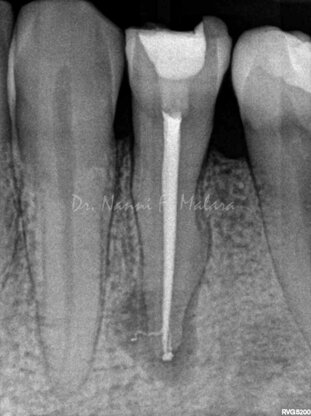

Premolare affetto da lesione periapicale (Alla radiografia si presenta come area scura intorno alla radice)

Terapia endodontica con sigillo tridimensionale del sistema canalare